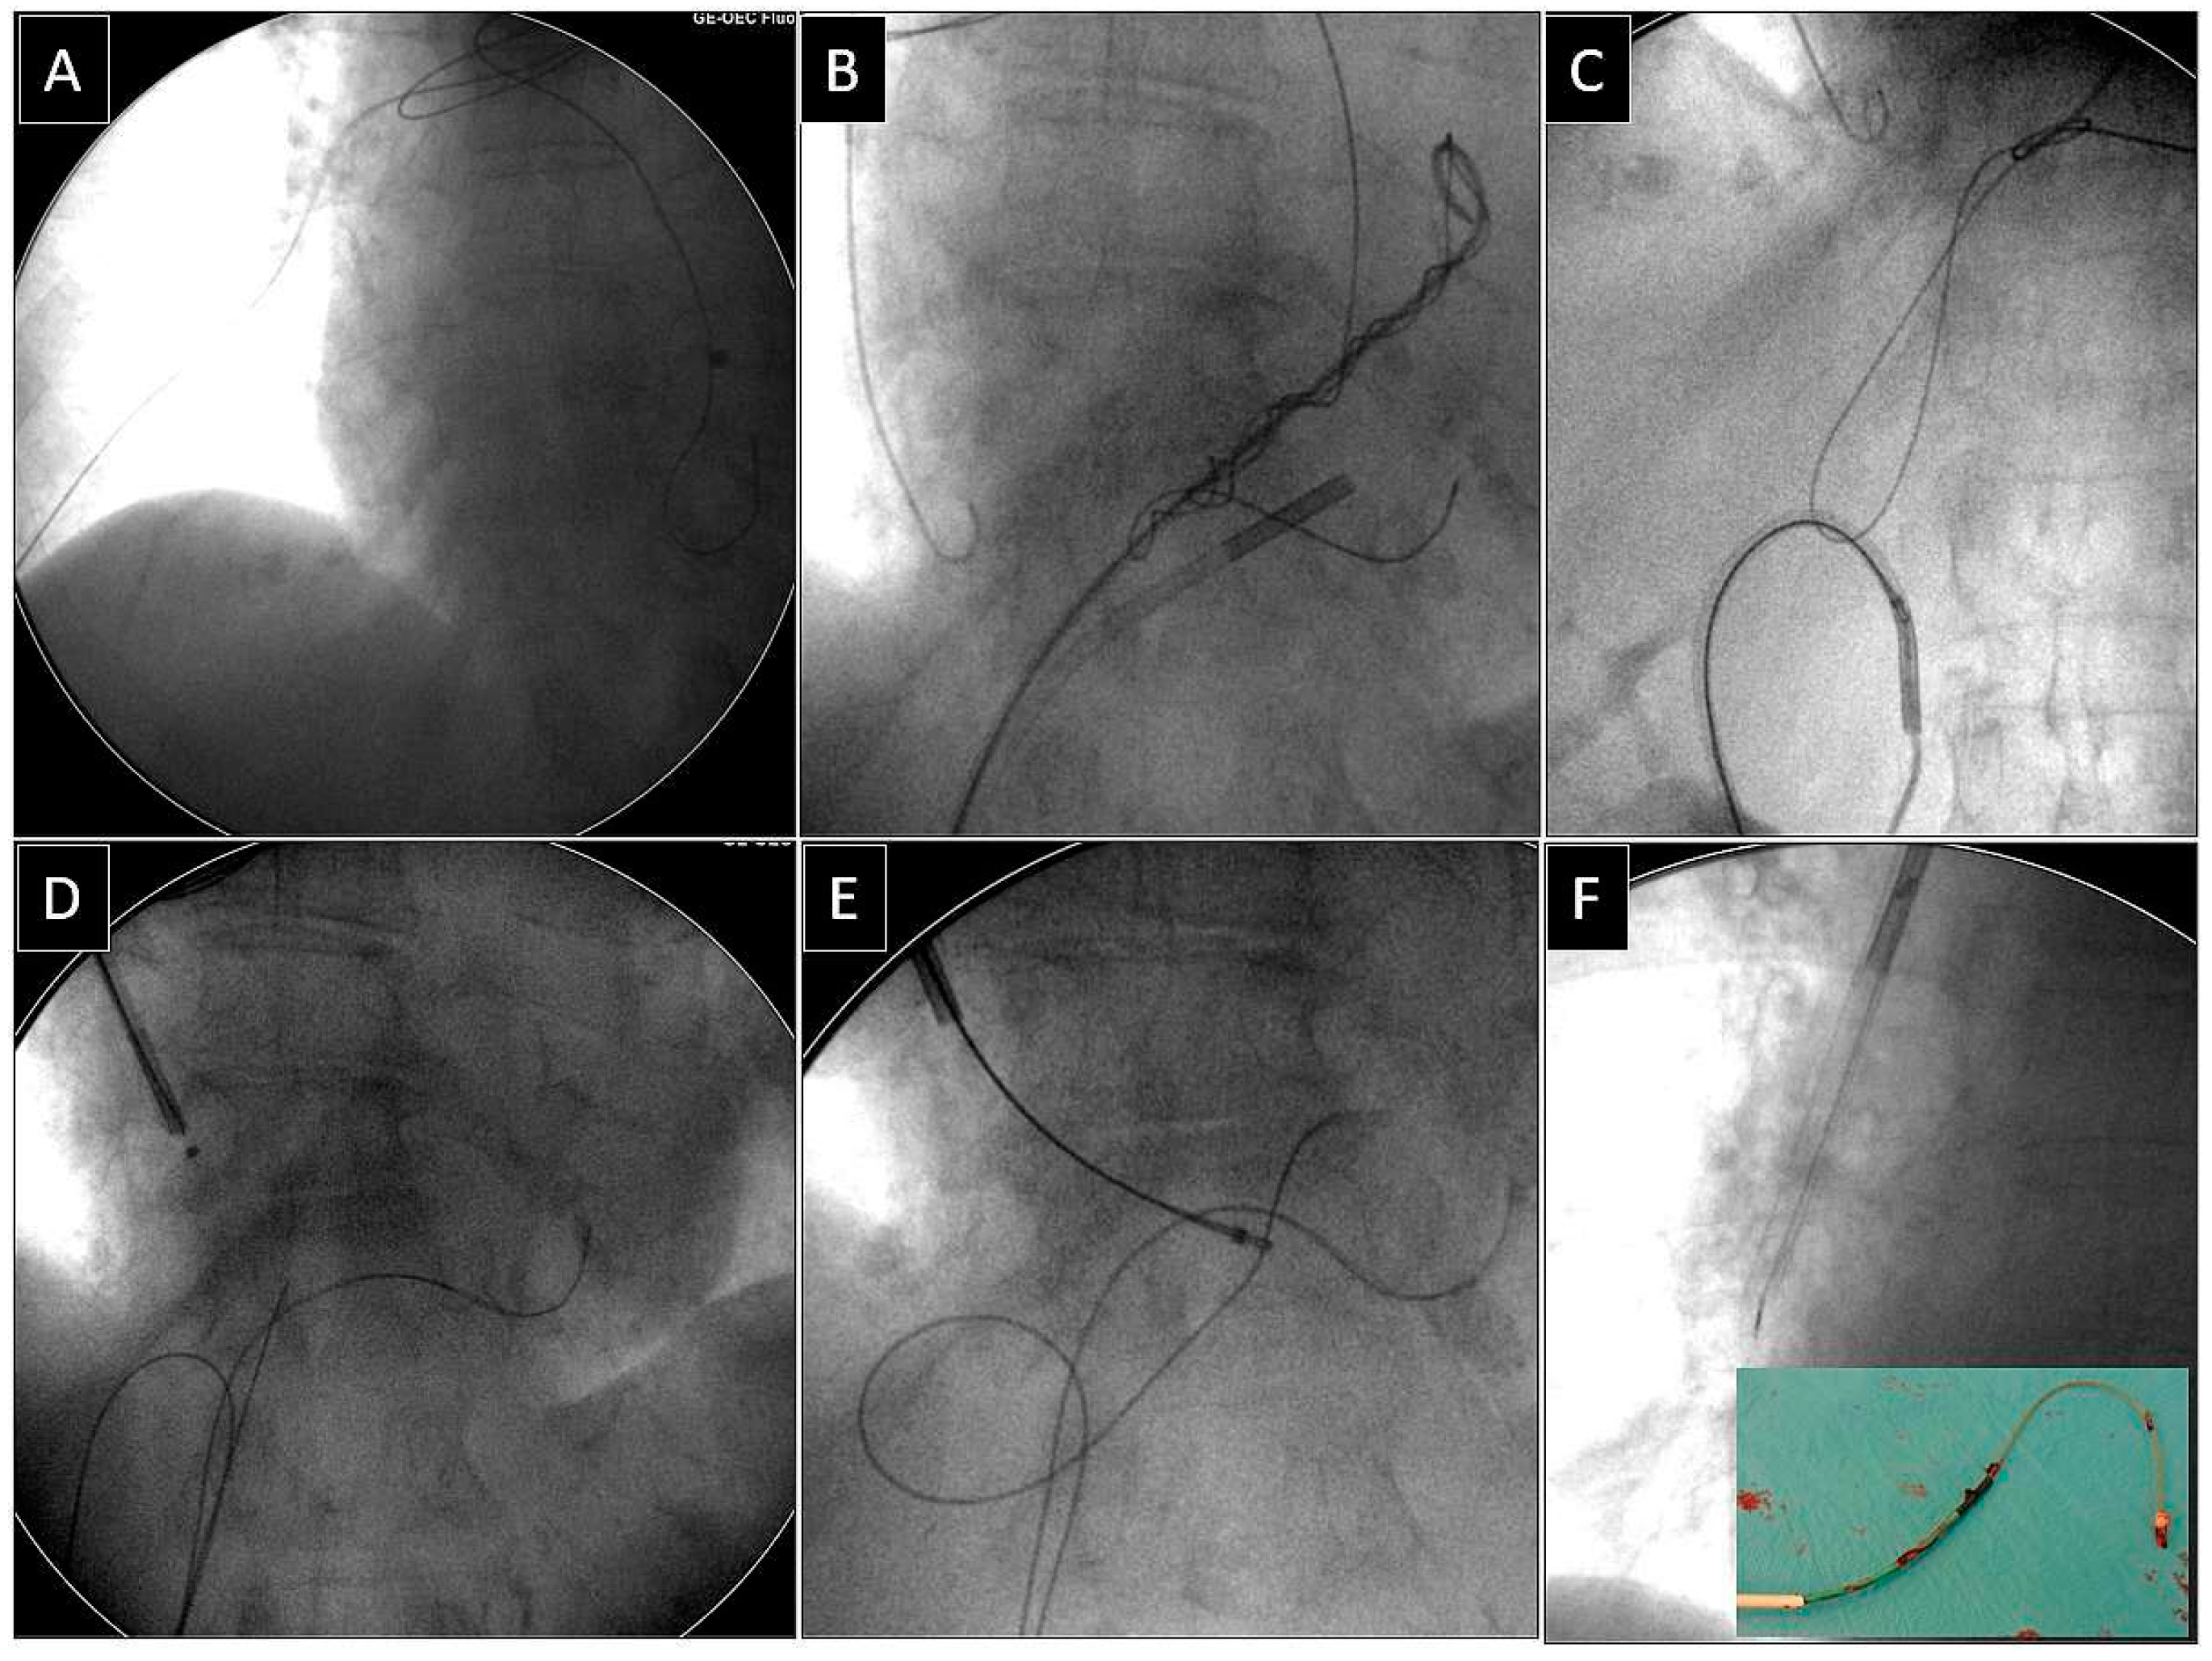

Extraction of Leads with Migrated Proximal Ends into the Cardiovascular Space

- Removal of such leads requires the use of different approaches and dedicated and non-dedicated tools.

| Superior approach | 6 (15.39) | 3 (23.08) p = 0.832 | 3 (23.08) p = 0.832 | 5 (71.43) p = 0.007 | 17 (23.61) |

| Combined approach | 3 (7.69) | 3 (23.08) p = 0.316 | 1 (7.67) p = 0.548 | 1 (14.29) p = 0.874 | 8 (11.11) |

| Femoral approach | 29 (74.36) | 7 (53.85) p = 0.298 | 8 (61.54) p = 0.596 | 1 (14.29) p = 0.001 | 45 (62.50) |

| Lasso/basket inside 13 FWS, NE (dilatation) | 31 (68.89) | Lasso/basket 13, FWS, NE—femoral approach (dilatation) | 31 (43.06) |

| Lasso/basket inside another large sheath (polypropylene) (dilatation) | 5 (11.11) | ||

| Lasso/basket inside transseptal sheath (only pulling) | 9 (20.00) | Lasso/basket another large sheath—femoral (dilatation) | 5 (8.33) |

| Loop femoral approach (pulling, end release) | 35 (77.78) | Lasso/basket in CS sheath—superior approach (pulling only) | 1 (1.39) |

| Pig-tail + winding and shifting femoral (end release) | 7 (15.56) | Lasso/basket only—superior approach (pulling only) | 3 (4.17) |

| Pig-tail femoral (end orientation) | 3 (6.67) | Cardiac surgery | 2 (2.28) |